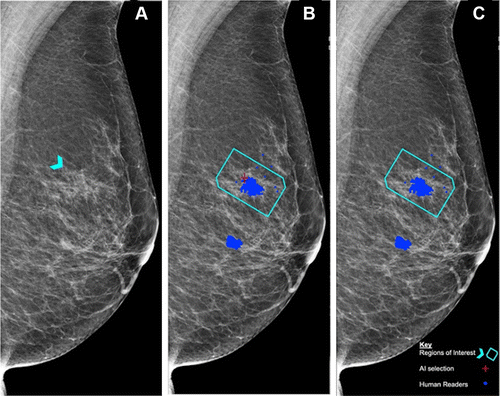

图 6:不同阈值对 AI 判断结果的影响

A:蓝色箭头为不对称区域,后鉴定为组织学 2 级导管癌;

B:AI 阈值为 2.91 时的检测结果,红色十字最终鉴定为真阳性;

C:AI 阈值为 3.06 时的检测结果,没有发现明显异常特征。